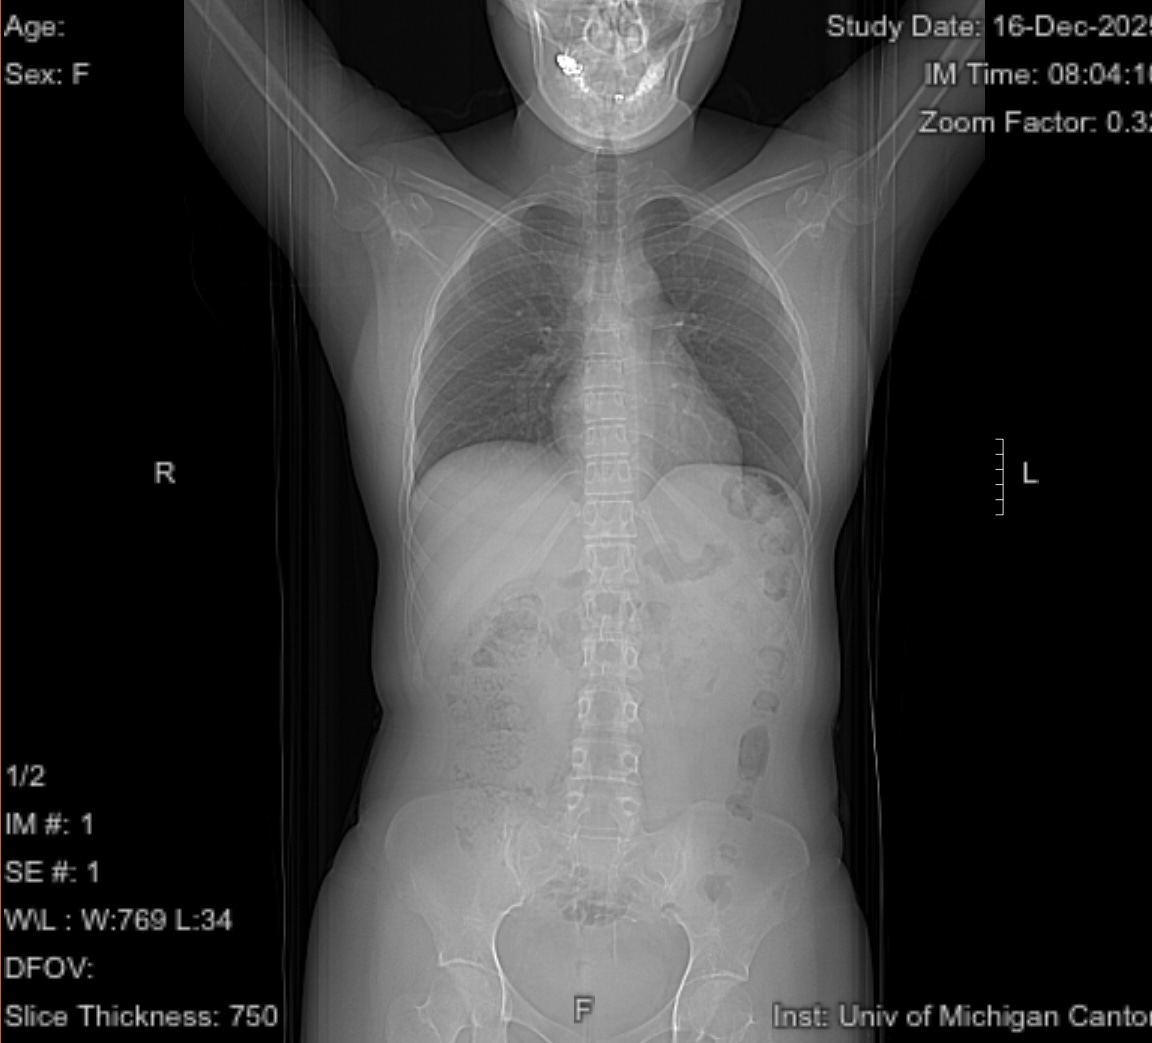

Love this. Wishing you all the best in your recovery 🖤 Ps, love that you included your CT scan topogram…that’s what I do for a living :)